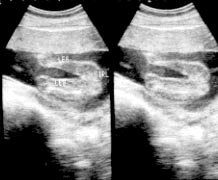

الأسبوع ال17